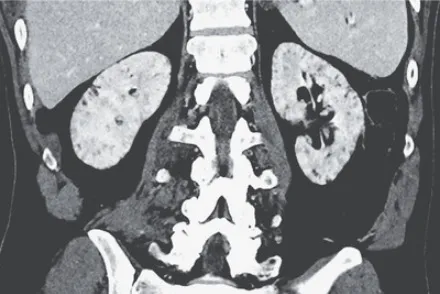

Uma causa incomum de hematúria glomerular intermitente!

Uma causa incomum de hematúria glomerular intermitente!

Hematúria pós infecção, caso clínicos para auxiliar no entendimento de causas glomerulares comuns e raras...